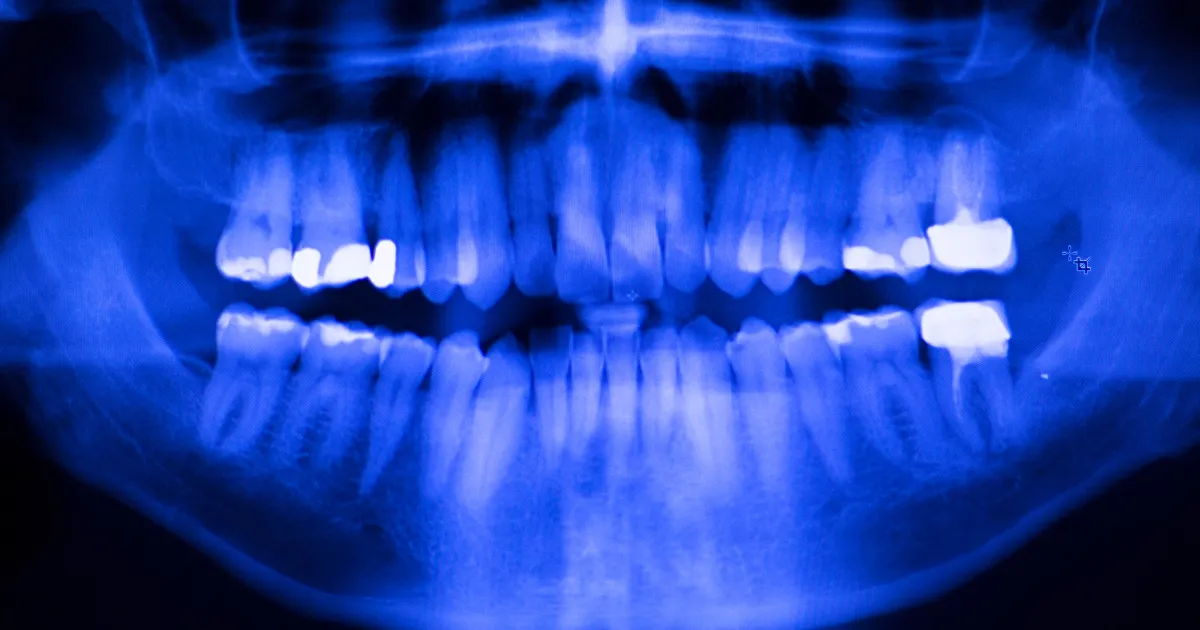

歯科ハミール高田88では、CT撮影や最新の3Dスキャナー「iTero」を導入しており、抜歯前の詳細な診断を行います。

これにより、歯の位置や形状、周囲の骨構造を正確に把握し、リスクを最小限に抑えた安全で確実な治療が可能です。

CTによる立体画像解析により、神経や血管の位置も明確にし、難易度の高い親知らずの抜歯にも対応しています。

この先端技術により、術後の合併症リスクも大幅に低減できます。